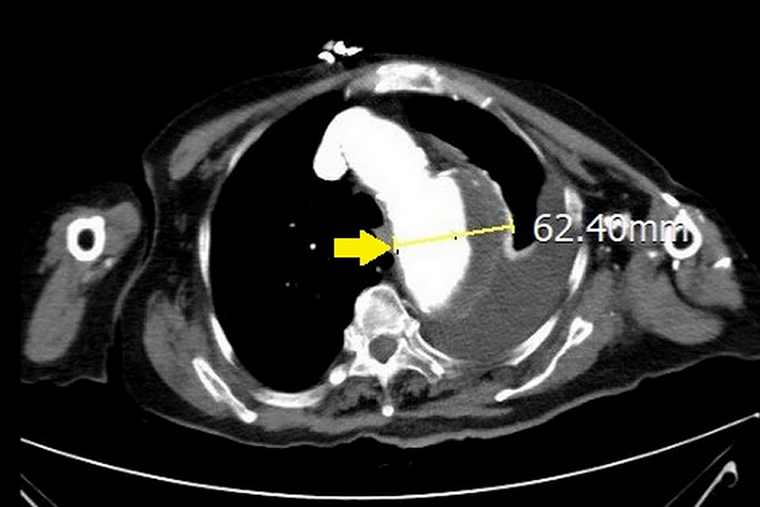

【NOW健康 楊芷晴/新北報導】高齡91歲陳女士平常有高血壓病史,但因季節交替氣溫變化大,血壓變得不穩定,日前因為胸痛、呼吸喘被送往急診。台北慈濟醫院心臟血管外科宋鎮宇醫師透過胸部X光檢查發現,陳女士的縱膈腔擴大且左側肋膜有大量積液,進一步電腦斷層追蹤發現是直徑約6公分大的胸主動脈瘤破裂合併血胸,當下緊急接受主動脈支架置放手術,術後一周平安出院,並經由藥物穩定控制血壓,目前已恢復正常生活。

▲電腦斷層追蹤發現是直徑約6公分大的胸主動脈瘤破裂合併血胸。(圖/台北慈濟醫院提供)

主動脈連結於心臟,負責將心臟輸出的血液供應至全身器官,是人體最大的動脈血管。所謂的主動脈瘤指的並非腫瘤,而是指主動脈有不正常膨大的現象,通常發生在胸部或腹部。正常而言,主動脈直徑約3公分,若膨大直徑超過1.5倍就是「主動脈瘤」。

尤其高血壓更是主要危險因子,會增加主動脈壁壓力,導致主動脈瘤增大,而有破裂風險。宋鎮宇指出:「主動脈瘤就像吹氣球一樣,被吹開之後就無法恢復。據統計,主動脈瘤的發生率為每十萬人口中有7人,其中將近8成為65歲以上的長者,且男性發生機會高於女性。若經發現,務必要接受治療,否則一旦破裂或剝離,死亡率達9成以上。」